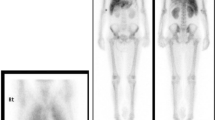

Octreoscan isolated somatostatin avid tissue in the pancreas and liver. Further investigations did not disclose evidence of multiple endocrine neoplasia.

Pathology confirmed a 14.5 cm well-differentiated, intermediate-grade NET with three mitotic figures per 10 HPF, Ki-67 index 10%, and positive cytoplasmic staining for PTHrP (Fig. 1).